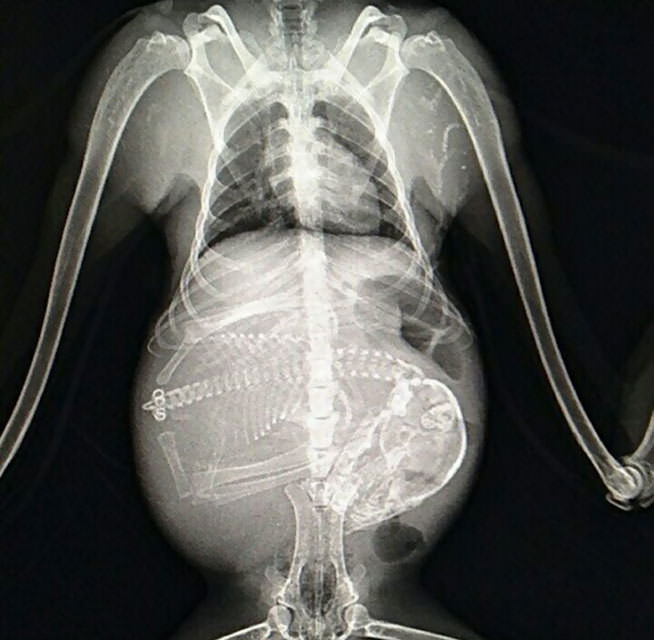

İnsanların ultrason görüntülerini görmeye hepimiz alışkınız. Ancak hamile hayvanların ultrason görüntüleri sizleri çok şaşırtacak.Kaplumbağa

İnsanların ultrason görüntülerini görmeye hepimiz alışkınız. Ancak hamile hayvanların ultrason görüntüleri sizleri çok şaşırtacak.